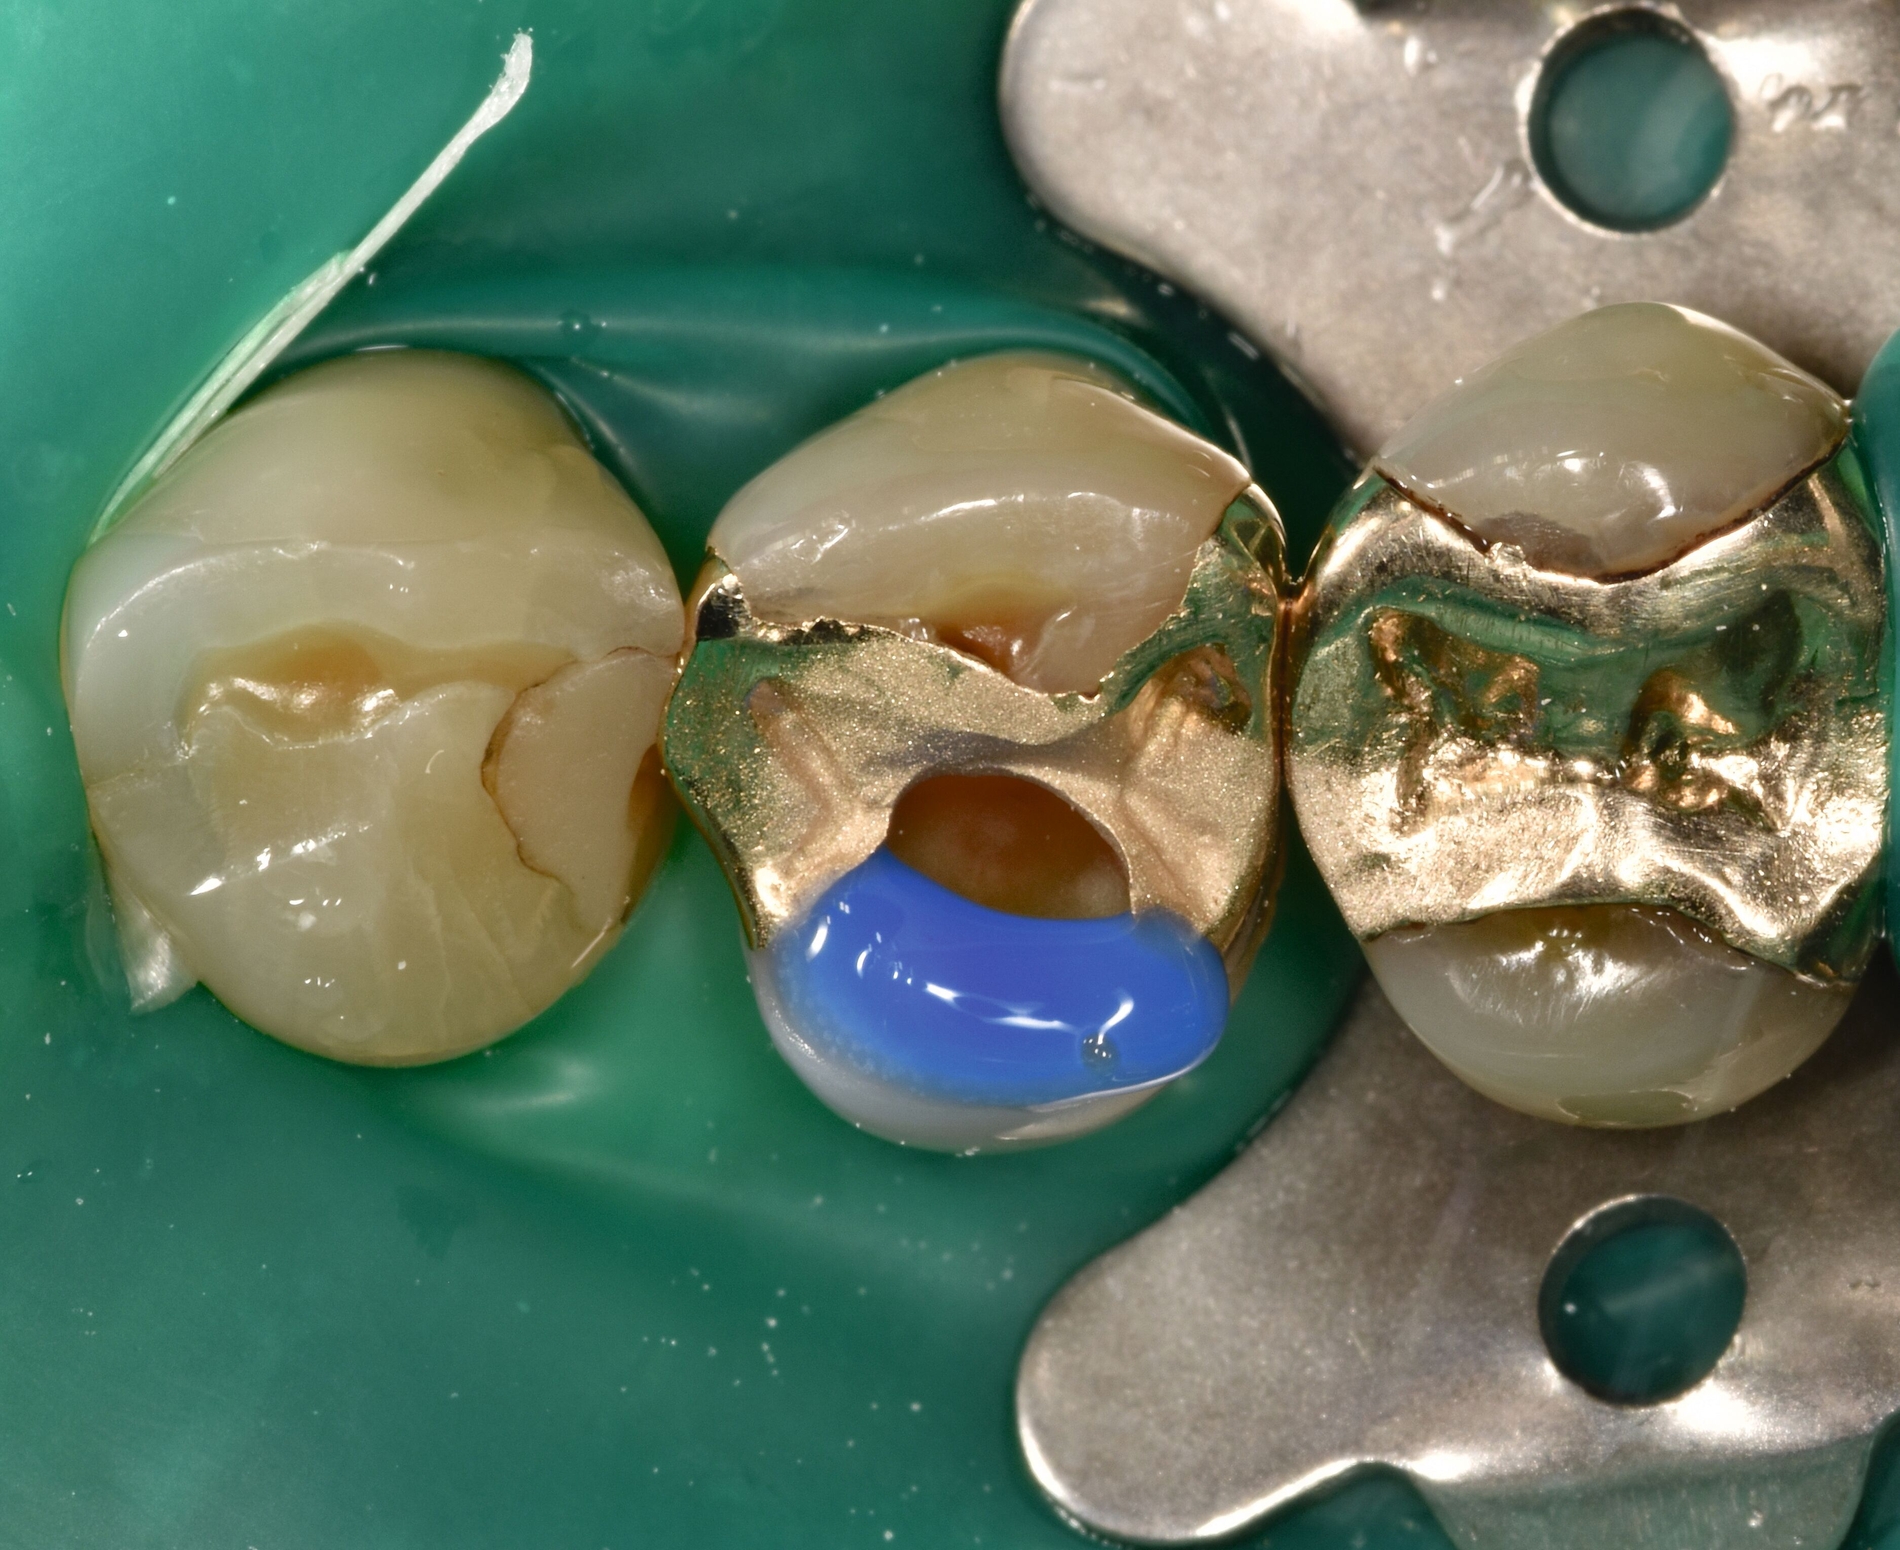

Nach Reinigung der Zähne und Bestimmung der Zahnfarbe wurde Kofferdam zur absoluten Trockenlegung angelegt. Mit rotierenden Instrumenten wurde ein Teil des Gussmetall-Inlays im sondierbaren Bereich entfernt und die Karies exkaviert (Abbildungen 2c und 2d). Anschließend wurden alle zu reparierenden Oberflächen (Gussmetall, Dentin und Schmelz) mit reinem Aluminiumoxid, Partikelgröße 50 µm (Rondoflex®/KaVo), unter Verwendung von Wasser abgestrahlt und danach gründlich mit Wasser abgespült (Abbildungen 2e und 2f). Die selektive Schmelzätzung erfolgte mit 37,5-prozentiger Phosphorsäure (Email Preparator®/Ultradent) für 30 Sekunden (Abbildung 2g). Nach Abspülen der Phosphorsäure mit Wasser wurde ein Universaladhäsiv (Clearfil Universal Bond Quick® / Kuraray Noritake) aufgetragen (Abbildung 2h, Glanz soll erhalten bleiben, Verdunstung einige Sekunden abwarten) und dann lichtpolymerisiert.